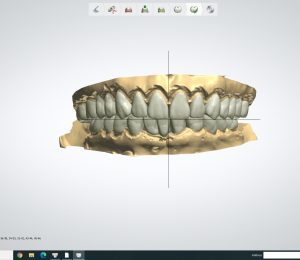

🚎🚎Sau khi được giải thích kĩ trên mẫu hàm, phim, hình ảnh và nhiều ngày suy nghĩ (chắc thấy bác sĩ gì mà nhỏ quá😅) chị đồng ý với kế hoạch điều trị gồm:

👉Tái lập khớp cắn và đường cong cắn khớp và mang răng tạm nhựa PMMA.